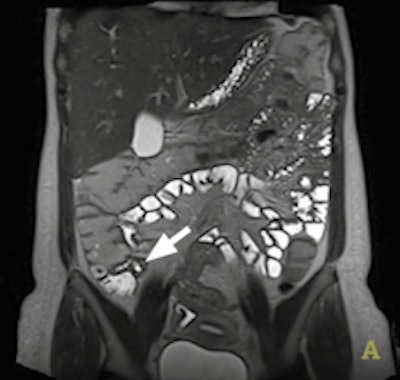

IVIM sequences can measure properties such as cellularity, perfusion, and vascular fraction, yielding qualitative and quantitative data. Images courtesy of Dr. Luis Martí-Bonmatí, PhD."Apparent diffusion coefficient (ADC) is simple and widely used but it is a bad matrix which introduces errors, due to the difference between centers and machines. ADC should be replaced with the IVIM matrix," Martí-Bonmatí said.

At today's session, ECR delegates will also learn how DWI state-of-the-art sequences can be standardized and optimized in clinical practice by using techniques like IVIM sequences to measure properties such as cellularity, perfusion, and vascular fraction, yielding qualitative and quantitative data.